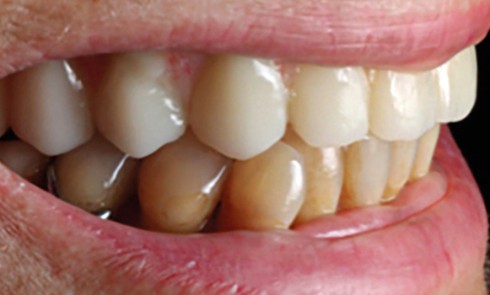

Article réservé à nos abonnés Le bridge collé canin en vitrocéramique : on adhère !

Grand Prix éditorial RC 2023 Dentisterie Esthétique 3e lauréats : Léa Massé, Cyprien Clark et Sonia Betin Léa Massé CCU-AH...